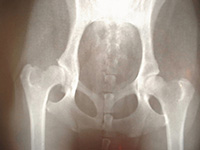

レントゲンを撮影したところ、股関節の坐骨という部分が完全に折れていました。

この場所は代謝性の疾患などで骨がうまくつくれなかったり脆かったりする以外は、交通事故や転落など強い衝撃が加わった場合に骨折することがあります。

また折れ方をみると、自然に骨折する位置ではなく、明らかに何か外力が加わって折れたと考えられました。